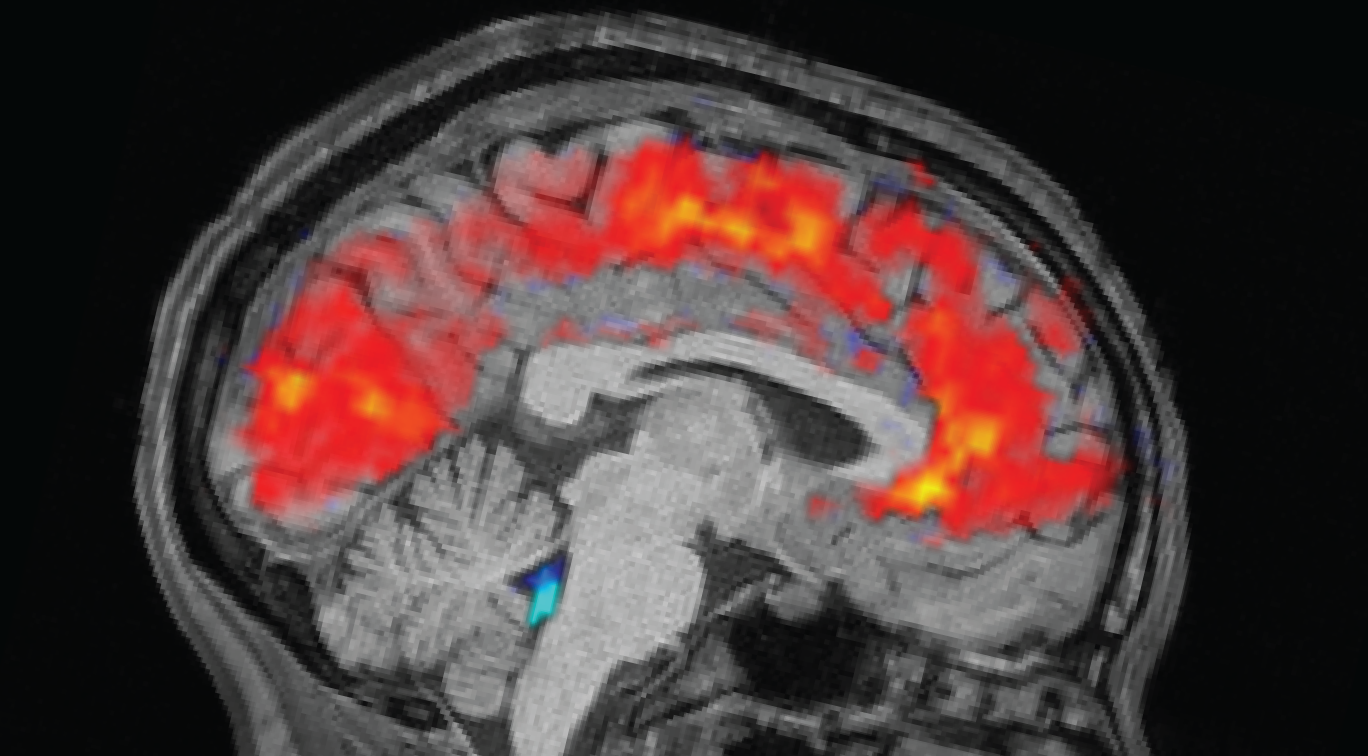

Scientists spot brains zoning out in real time

Tired brains flush more often. (Image credit: Zinong Yang)

Well, scientists finally have a physiological explanation for why this happens when you’re sleep-deprived: Your brain is literally flushing out cerebrospinal fluid, making it nigh-impossible for you to concentrate. The exact functional reason for this is still unclear, but scientists think it could have something to do with sleep-deprived brains switching into sleep-like states, possibly as a form of waking brain waste disposal you missed out on the night before.